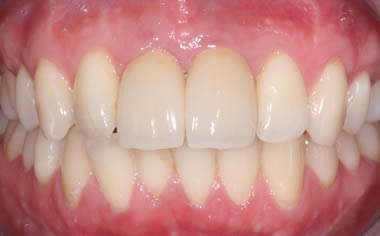

Missing upper front tooth replaced by dental implant and crown